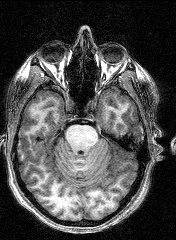

The last session involved several MRI and fMRI scans while completing tasks in the noisy environment of the scanner. Thanks to a friend who worked at the Institute, I was able to secure a copy of the raw data and an application to turn it into images, some of which are displayed here.

The images to the right are virtual 'slices', taken horizontally, starting from the top and working down. Cerebrospinal fluid is dark, the white matter appears light.

Medical images such as these are easy to come by on the internet, but having images of your own brain brings a humbling perspective.